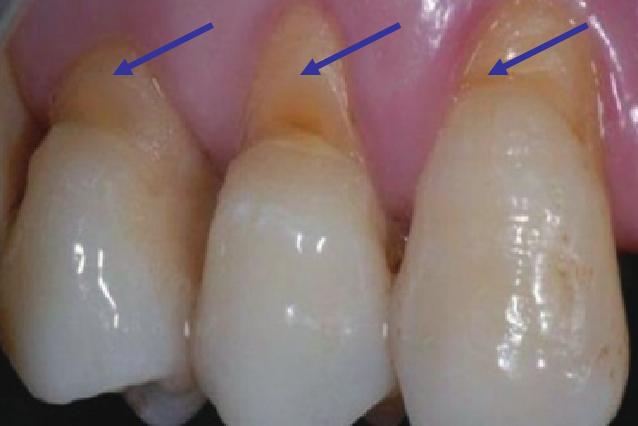

请对照下面的图片,看看您的牙齿根部是否隐约有深浅不一的凹槽,如果有,那就得当心了。有些人牙齿常常遇凉酸痛,总以为是蛀牙,殊不知很有可能是这些凹槽也就是医学上称作的“楔状缺损”所导致。

楔状缺损是牙齿唇、颊侧颈部硬组织发生缓慢消耗所致的缺损,典型的缺损由两个夹面组成,口大底小,呈楔形,故而得名。